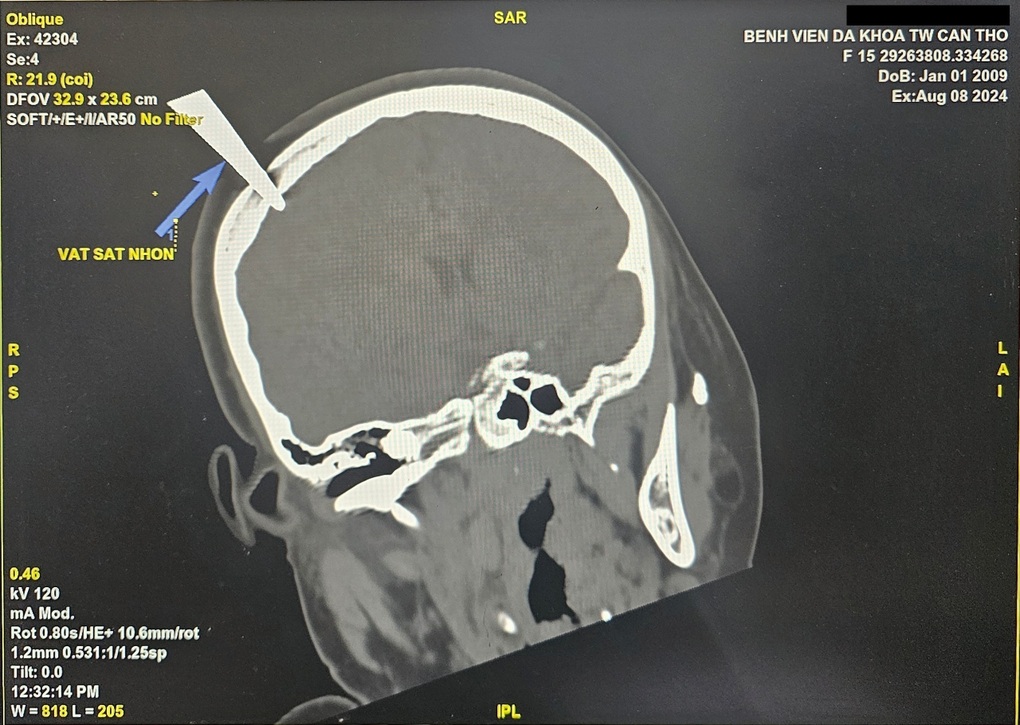

Qua kết quả chụp cắt lớp vi tính, các bác sĩ Bệnh viện Đa khoa Trung ương Cần Thơ nhận thấy có dị vật cản quang xuyên sọ đỉnh phải, có hình ảnh kim loại; vết thương vùng đỉnh phải của T. thủng do mũi kéo đâm 0,5cm.

Attached Thumbnails

Click image for larger version

Name:	hinh-anh-di-vat-sac-nhon-tren-phim-chup-cat-lop-1723201575677.jpg